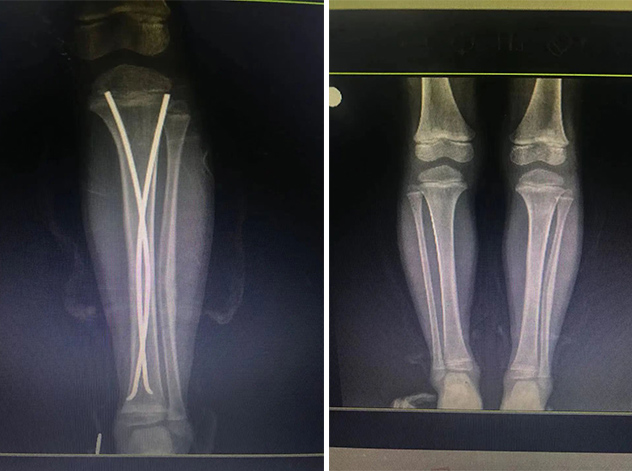

經(jīng)拍片顯示,睿睿左脛腓骨中段粉碎性骨折。接診的我院骨科中心主任羅軍建議其入院接受手術(shù)治療。

在接下來的康復(fù)過程中,睿睿非常配合,恢復(fù)的非常好。今年4月12日,睿睿拆除了左腿里的彈性釘。

拆前拆后對比

據(jù)羅主任介紹,兒童骨折絕不是成人骨折的縮小版。兒童的不穩(wěn)定性脛骨骨折或雙側(cè)脛骨骨折,保守治療很難達(dá)到理想復(fù)位,可能會(huì)造成肢體不等長、成角旋轉(zhuǎn)畸形、肌肉萎縮等并發(fā)癥。而彈性髓內(nèi)釘?shù)膽?yīng)用,正好解決了患者和醫(yī)生所擔(dān)心的問題,既理想地固定了骨折,又不影響肢體美觀,可謂一舉兩得。“彈性髓內(nèi)釘”技術(shù)可在保護(hù)骺板不受損傷的前提下,利用多點(diǎn)固定的原理,微創(chuàng)、有效地治療3—15歲的四肢長骨骨折患兒。手術(shù)在C型臂全程引導(dǎo)下,只需在骨折遠(yuǎn)、近端各切一2—3cm切口打入彈性髓內(nèi)釘,創(chuàng)傷極小,不影響孩子的骨骼發(fā)育,對于骨折的愈合以及孩子以后骨骼發(fā)育影響小。相比之下,既有效避免了切開復(fù)位鋼板內(nèi)固定創(chuàng)傷大、疤痕大等缺點(diǎn),又有效避免了支架外固定鋼針外露、不易護(hù)理等弊端。